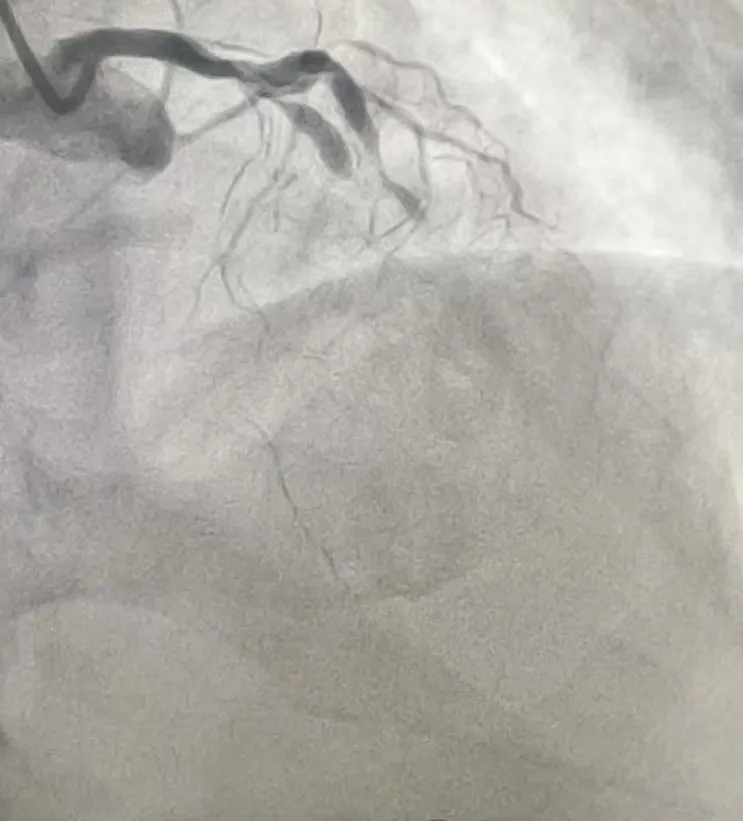

经过2小时的紧张奋战,前降支和回旋支成功开通,闭塞的血管重新“通车”,濒死的心肌迎来“救命血”。术中造影显示,支架贴壁良好,血流恢复至正常(TIMI3级),手术圆满成功。

(术后影像)